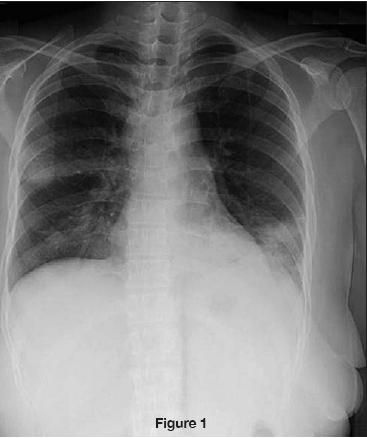

The patient's chest radiograph revealed left lower lobe, lingular, and right upper lobe infiltrates (Figure 1). A CT scan of the chest revealed 2.8-cm right hilar adenopathy and 2.0-cm left hilar adenopathy with patchy areas of consolidation in the right upper, right middle, left lower, and lingular lobes (Figure 2).

The most common presentation of Nocardia infection involves pulmonary manifestations, which are seen in more than two thirds of cases.3 The radiographic appearance is protean. Parenchymal disease may include irregular nodules (with large nodules usually cavitating), reticulonodular or diffuse pneumonic infiltrates, and pleural effusions. The pneumonic infiltrates are necrotizing and poorly contained, resulting in erosion into bony structures. The radiological findings may be similar to those of tuberculosis-upper lobe cavitary infiltrates are commonly seen.